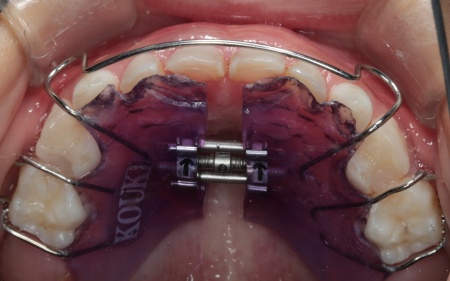

今回の治療では、床(しょう)矯正装置のひとつである「拡大床」という装置を使用した治療法をおすすめしました。

床矯正装置とは、プラスチックの土台部分がある取り外し式の矯正装置の総称です。拡大床は、そのなかでも顎の幅を拡大することを目的とした装置で、中央に組み込まれたスクリューと呼ばれるネジを少しずつ回すことで、顎の横幅を徐々に広げていきます。

まずは患者様専用の拡大床を製作し、装着を開始します。

治療中は、スクリューを少しずつ回すことで顎の骨が徐々に横方向に拡大されていき、永久歯が生えるためのスペースを十分に確保することができました。

治療中